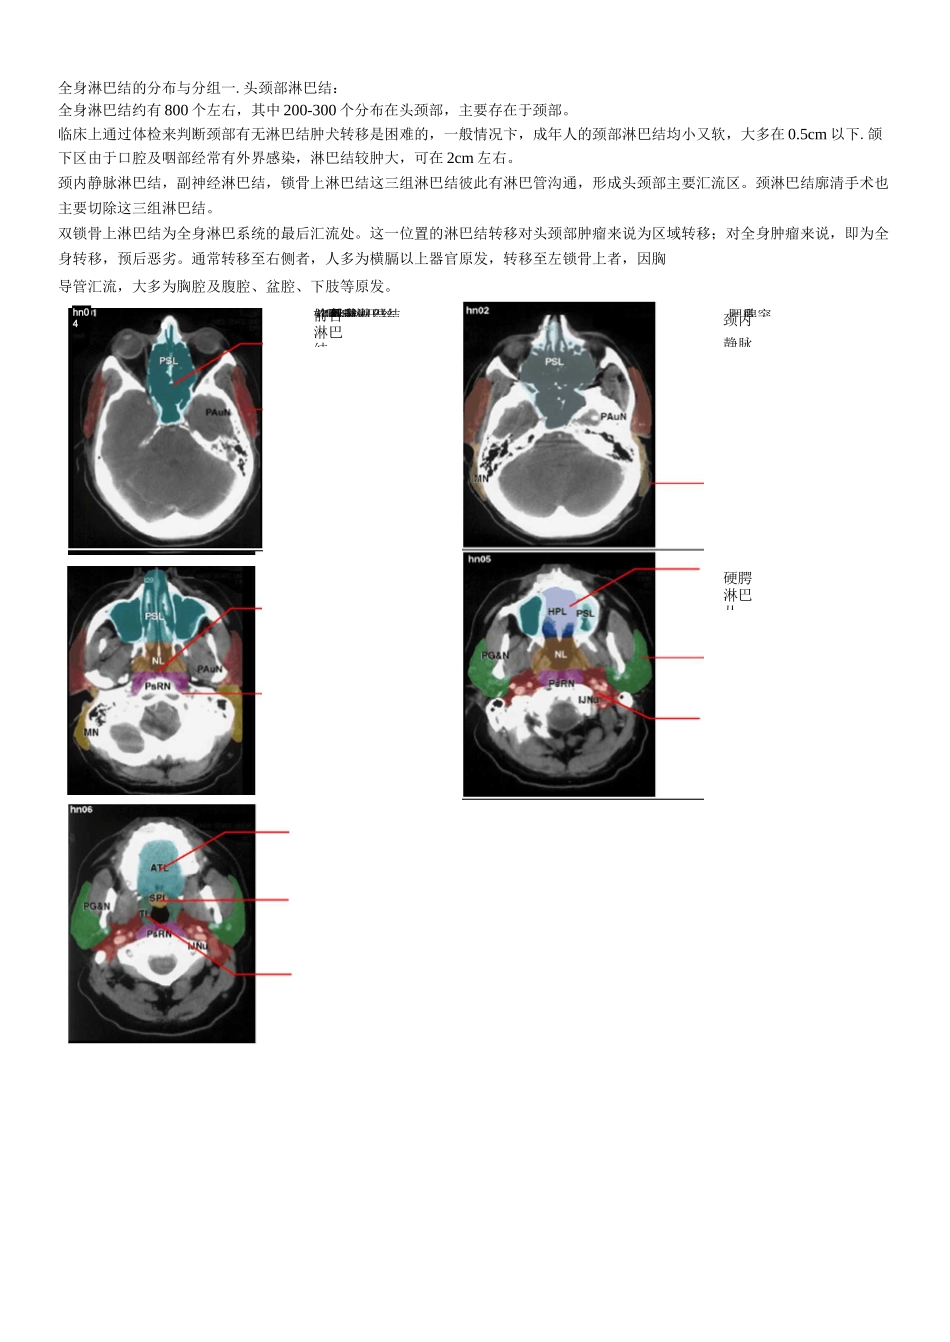

鼻旁耳前鼻咽淋巴结咽后淋巴结乳突全身淋巴结的分布与分组一.头颈部淋巴结:全身淋巴结约有 800 个左右,其中 200-300 个分布在头颈部,主要存在于颈部。临床上通过体检来判断颈部有无淋巴结肿犬转移是困难的,一般情况卞,成年人的颈部淋巴结均小又软,大多在 0.5cm 以下.颌下区由于口腔及咽部经常有外界感染,淋巴结较肿大,可在 2cm 左右。颈内静脉淋巴结,副神经淋巴结,锁骨上淋巴结这三组淋巴结彼此有淋巴管沟通,形成头颈部主要汇流区。颈淋巴结廓清手术也主要切除这三组淋巴结。双锁骨上淋巴结为全身淋巴系统的最后汇流处。这一位置的淋巴结转移对头颈部肿瘤来说为区域转移;对全身肿瘤来说,即为全身转移,预后恶劣。通常转移至右侧者,人多为横膈以上器官原发,转移至左锁骨上者,因胸导管汇流,大多为胸腔及腹腔、盆腔、下肢等原发。hn04前舌淋巴结软腭淋巴结扁桃硬腭淋巴丛腮腺颈内静脉卜•咽后壁和咽后淋巴结声门下淋巴系统左颈气管二.RTOG 颈淋巴结分区界定分区上界下界前界后界外侧界内侧界la硕舌骨肌,下颌骨基缘切面舌骨体切面下颌骨联合,颈阔肌舌骨体二腹肌前腹的内侧缘不存在声门梨状喉前淋巴结声门颈气管前淋巴左颈气管旁淋巴结锁骨PG&食管周闱环状软骨后淋巴丛体中线Ib下颌舌骨肌,下颌下腺上缘舌骨中心平面下颌骨联合,颈阔肌下颌下腺后缘下颌骨基底缘/内侧缘,颈阔肌二腹肌前腹外侧缘Ila颈 1 椎体横突下缘舌骨体下缘下颌下腺后缘,颈内动脉前缘,二腹肌后腹后缘颈内静脉后界胸锁乳突肌内侧缘颈内动脉内侧缘,脊柱旁肌(肩胛提肌)IIb颈 1 椎体横突下缘舌骨体下缘颈内静脉后缘胸锁乳突肌后界胸锁乳突肌内侧缘颈内动脉内侧缘,脊柱旁肌(肩胛提肌)III舌骨体下缘环状软骨下缘胸骨舌骨肌后外侧缘,胸锁乳突肌前缘胸锁乳突肌后缘胸锁乳突肌内侧缘颈内动脉内侧缘,脊柱旁肌(斜角肌〉IV环状软骨下缘胸锁关节上两公分胸锁乳突肌前内缘胸锁乳突肌后缘胸锁乳突肌内侧缘颈内动脉内侧缘,脊柱旁肌(斜角肌〉V舌骨体上缘CT 上出现颈部横向血管胸锁乳突肌后缘斜方肌前外侧界颈阔肌,皮肤脊柱旁肌(肩胛肌,头夹肌〉VI甲状软骨体下缘胸骨柄皮肤,颈阔肌气管食管间隙甲状腺内缘,皮肤和胸锁乳突肌前内侧缘不存在咽后淋巴结颅底舌骨体上缘咽部粘膜下筋膜椎前肌(颈长肌、头长肌)颈内动脉内侧缘体中线分区上界下界前界后界外侧界内侧界咽后淋巴结颅底舌骨体上缘咽部粘膜下筋膜椎前肌(颈长肌.头长肌)颈内动脉内侧缘体中线...